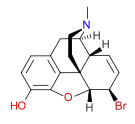

Morphides

- α-Chlorocodide (= chlorocodide)

- β-Chlorocodide

- α-Chloromorphide (= chloromorphide)

- Bromocodide

- Bromomorphide

- Chlorodihydrocodide

- Chloromorphide

- Codide

Structures

| Morphides | ||||

|---|---|---|---|---|

α-chlorocodide α-chlorocodide |

β-chlorocodide β-chlorocodide |

Bromomorphide Bromomorphide | ||

Chlorodihydrocodide. Chlorodihydrocodide. |

Chloromorphide Chloromorphide |

Codide Codide | ||